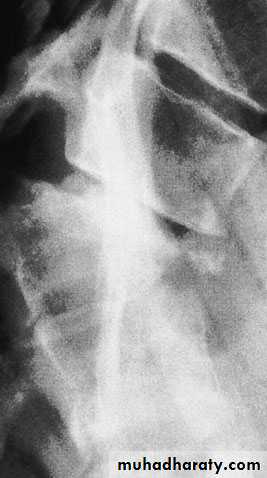

Flexion–compression injury

This is by far the most common vertebral fracture and is due to severe spinal flexion, though in osteoporotic occur with minimal trauma.

The posterior ligaments usually remain intact,

Pain may be quite severe but the fracture is usually stable.

Neurological injury is extremely rare.

Those with moderate wedging (loss of 20–40 per cent) of anterior vertebral height) and a stable injury can be allowed up after a week, wearing a thoracolumbar brace or a body cast applied with the back in extension.

If loss of anterior vertebral height is greater than 40

per cent, it is likely that the posterior ligaments have

been damaged by distraction and will be unable to